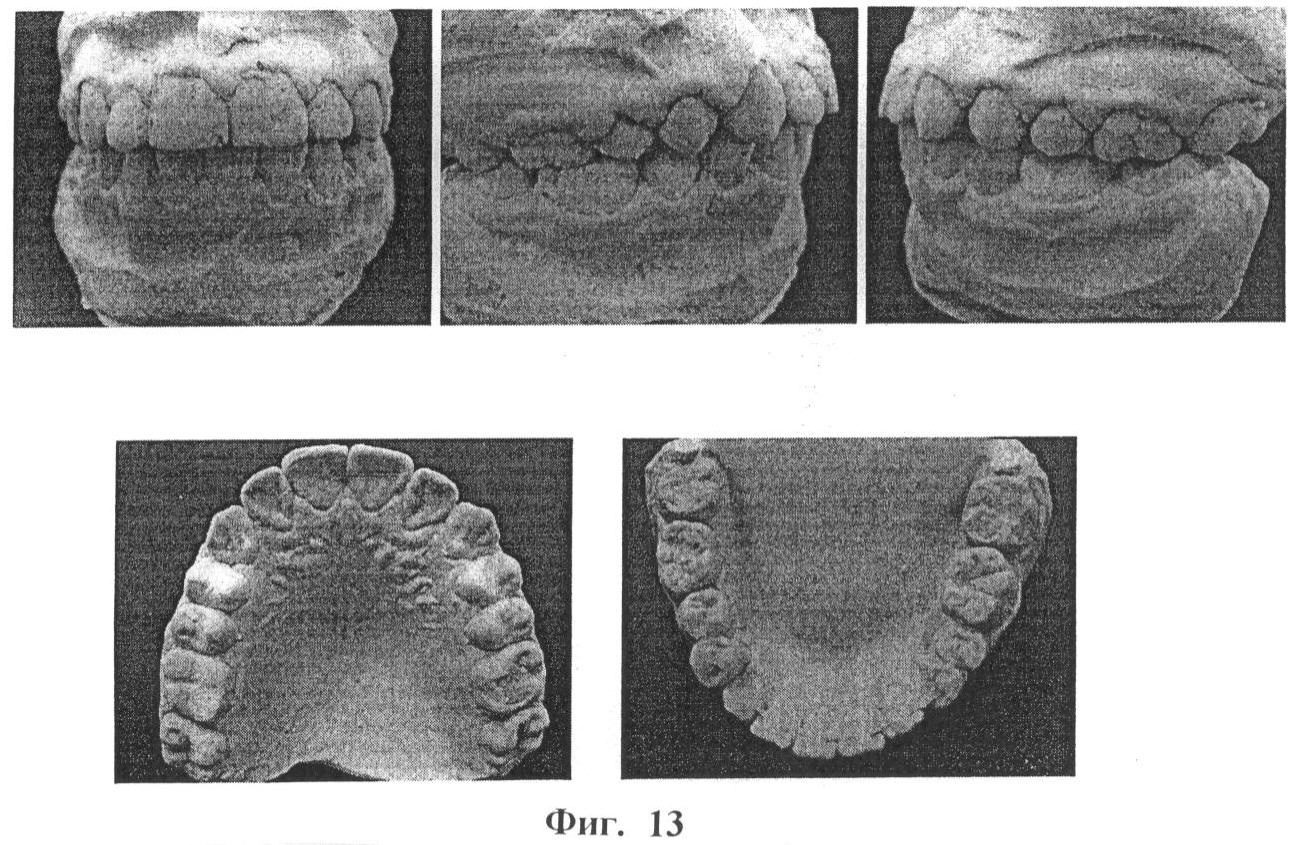

Изобретение иллюстрируется фотографиями, где на фиг.1 и 2 показаны зубные ряды верхней и нижней челюстей пациентки А., на фиг.3 – расположение несъемного аппарата с тремя направляющими на верхней челюсти для расширения и удлинения верхнего зубного ряда (стрелками указано направление активации винта), на фиг.4 показана реплантация клыка и премоляра, фиксация брекетов на эти зубы, шинирование в зубном ряду при помощи ортодонтической дуги и металлических лигатур, разобщение прикуса за счет окклюзионных накладок из стеклоиономерного цемента на 36 и 46 зубы, на фиг.5 показаны фотографии зубных рядов пациентки А. после ортодонтического лечения, на фиг.6 показана фиксация брекетов, колец и небного бюгеля на зубы верхней челюсти, на фиг.7 – зубные ряды пациентки А. верхней и нижней челюстей после ортодонтического лечения, на фиг.8 – ортопантомограмма пациентки А. до ортодонтического лечения, на фиг.9 – ортопантомограмма пациентки А. через 6 месяцев после реплантации клыка и премоляра, на фиг.10 – ортопантомограмма пациентки А. после ортодонтического лечения, на фиг.11 – телерентгенограммы пациентки А. до и после ортодонтического лечения, на фиг.12 и 13 – гипсовые модели пациентки А. до и после ортодонтического лечения соответственно.

Нестандартность проведенного комплексного лечения состояла в применении брекет-системы и несъемного аппарата с тремя направляющими (винт Бертони) для расширения и удлинения верхнего зубного ряда и реплантации клыка и премоляра с использованием синтетического коллаген-апатитового материала «ЛитАр» для оптимизации репаративного остеогенеза. У данной пациентки проведена компьютерная томография верхней и нижней челюсти, ортопантомография и телерентгенография, изучение гипсовых моделей челюстей до и после ортодонтического лечения (фиг. 9, 10, 11, 12, 13, 14).